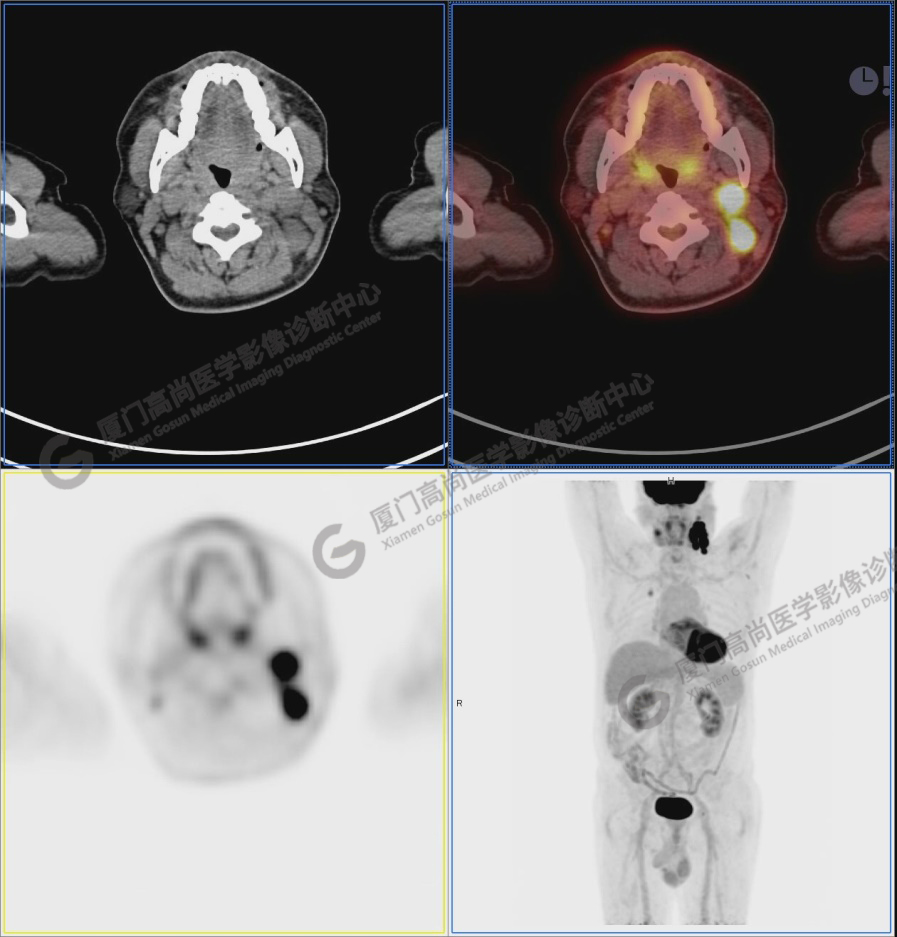

圖1:PET/CT全身圖像

圖2:雙側(cè)頸部多發(fā)增大淋巴結(jié),代謝不同程度增高,考慮為轉(zhuǎn)移。